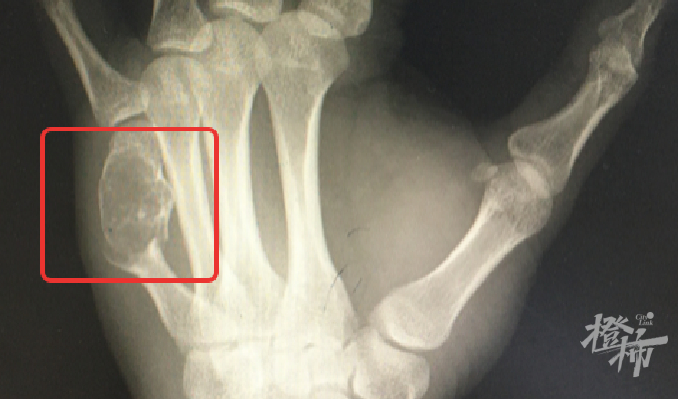

”这可不是一般的键盘手,你左手这根骨头里的东西,其实是内生性软骨瘤,它把你正常的骨头都‘融’成‘豆腐渣’了,所以骨头才会一碰就裂开,需要刮除肿瘤组织同时固定骨折的掌骨。”  杭州市第三人民医院骨科马伟副主任医师指着X片对黄先生解释道。